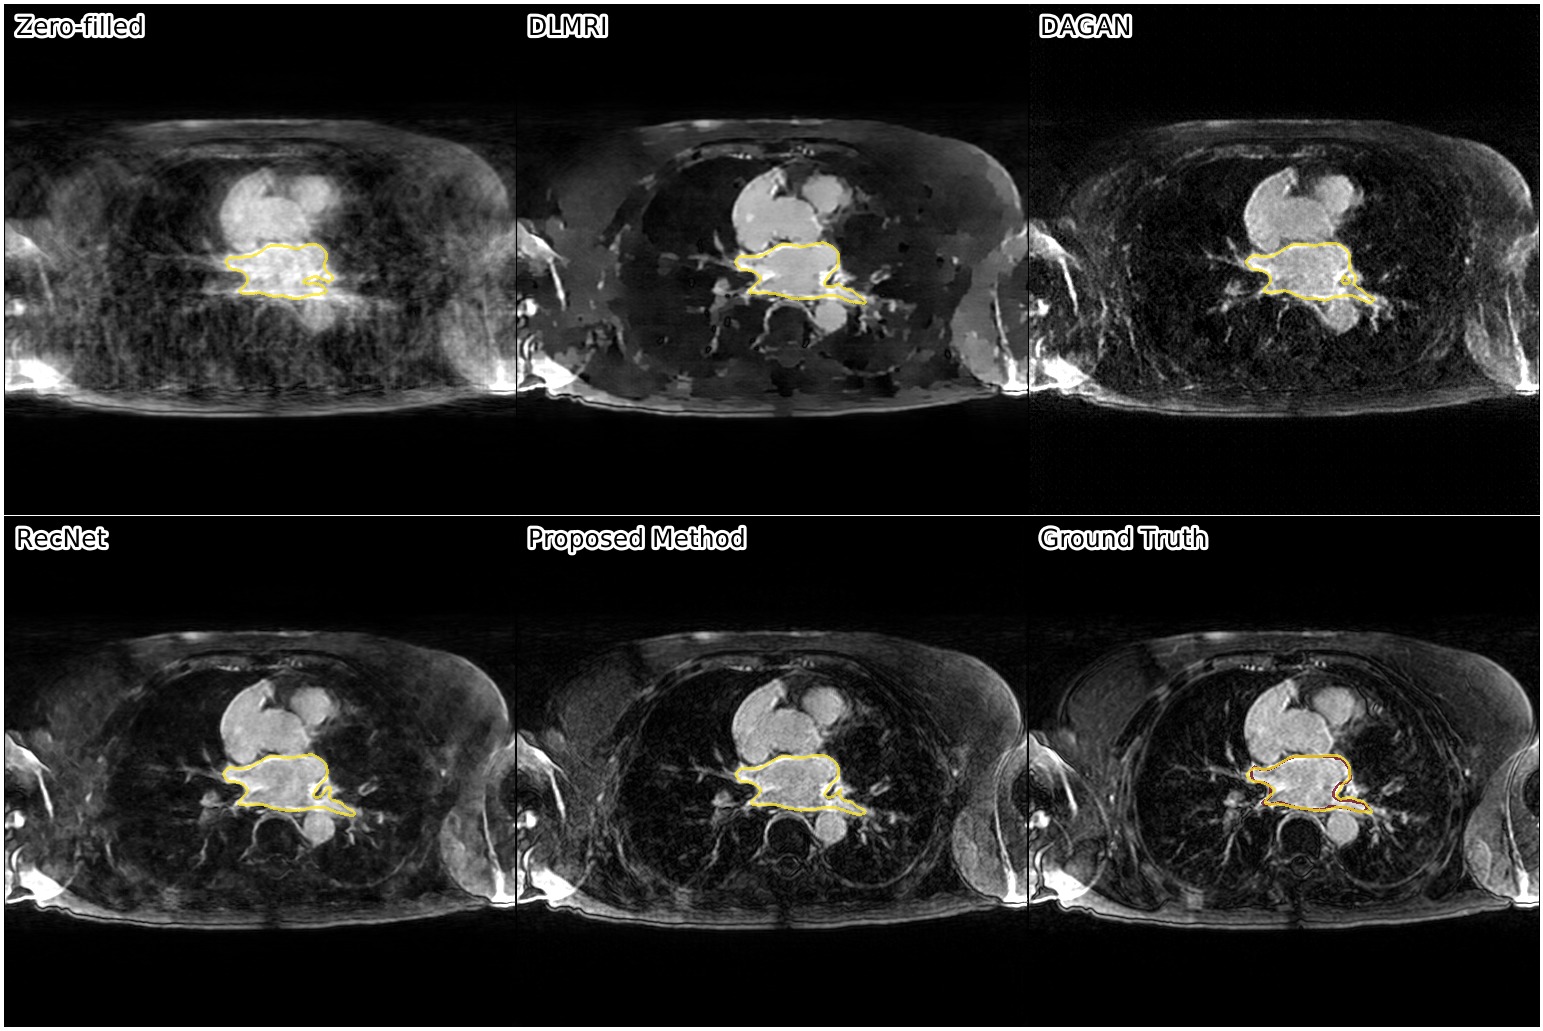

The following images show more samples for 8-fold undersampling. For each of the seven patients of the test set, a random slice showing the left atrium was selected. The contour of the predicted segmentation of left atrium is shown in yellow, the contour of the ground truth segmentation in red.